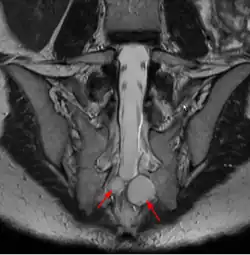

| MRI image showing a Tarlov cyst | |